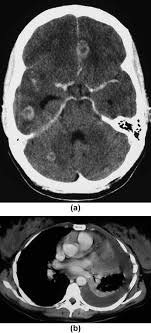

One of the ways in which ovarian cancer can cause severe confusion in diagnosis is the possibility of causing positive pregnancy tests. Scan showed adenomyosis and ovarian cyst. Every year, 7,000 women are diagnosed with ovarian cancer and 4,300 women lose their lives to it. Baby brain, or forgetfulness during pregnancy happens to a lot of mothers, and it usually goes away after the pregnancy. The outlook for ovarian cancer varies, depending on its stage and type. The symptoms that can be common to both ovarian cancer and pregnancy are as follows: Of all types, it is the epithelial ovarian cancer that accounts for about 85% of 90% of the cases of ovarian cancer, being the most. Each year, according to the centers for disease control and prevention (cdc). Pregnancy suspends the period for nine months, origa explains. Most ovarian cysts resolve within a few months, often without treatment. Doctors in 147 specialties are here to answer your questions or offer you advice, prescriptions, and more. Aarti abraham ( obgyn) on alesse birth control. I had 10 or 12 inches of colon removed.

Doctors at two hospitals thought christine coppa's terrible pain and leg tingling were caused by a small ovarian cyst. Pelvic discomfort, abdominal swelling and/or bloating, urinary frequency, constipation, abnormalities in menstruation, nausea, and vomiting, and fatigue. Every year, 7,000 women are diagnosed with ovarian cancer and 4,300 women lose their lives to it. First is, the ovarian cancer is not extremely common, so it's not the first thing that most doctors think about. Unfortunately, only about 20 percent of. Although ovarian cancer occurs at higher rates in women with endometriosis, the overall lifetime risk is low to begin with. The symptoms that can be common to both ovarian cancer and pregnancy are as follows: After pleading with one doctor to finally listen to her, she got a much more.

One of the ways in which ovarian cancer can cause severe confusion in diagnosis is the possibility of causing positive pregnancy tests.